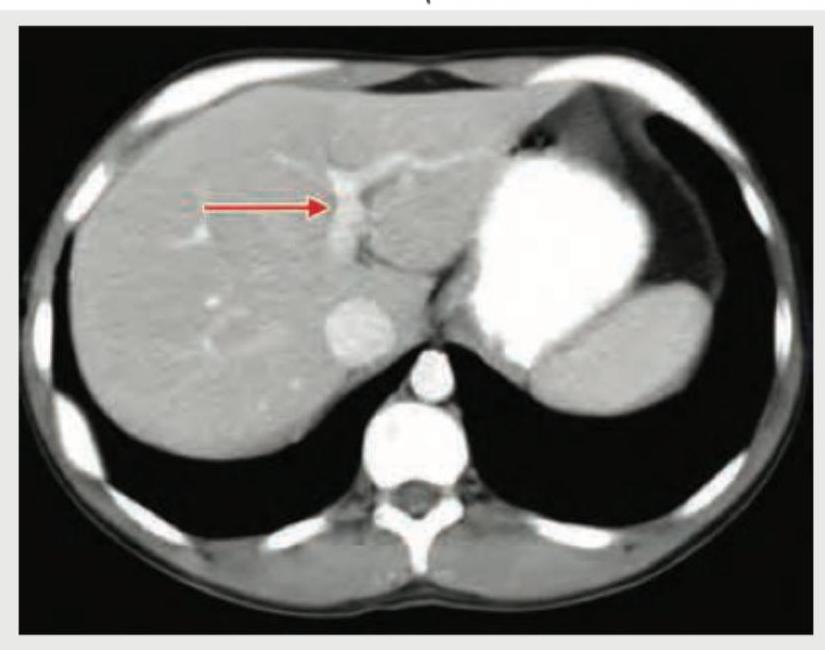

Identify the structure shown in CT abdomen section. (Recent NEET Pattern 2018-19)

Explanation: ***Portal vein*** - The arrow points to a vessel receiving blood from the splenic and superior mesenteric veins, which is characteristic of the **portal vein** entering the **liver parenchyma**. - The portal vein is typically seen anterior to the **inferior vena cava** and posterior to the **common hepatic artery** at this level. *Inferior vena cava* - The **inferior vena cava (IVC)** is a large, retroperitoneal vessel located posterior to the liver and to the right of the aorta. - The structure indicated by the arrow is clearly within the liver substance, not in the typical position of the IVC. *Splenic vein* - The **splenic vein** runs horizontally behind the body of the pancreas and joins with the superior mesenteric vein to form the portal vein. - The vessel shown is within the liver, distal to the formation of the portal vein. *Superior mesenteric vein* - The **superior mesenteric vein (SMV)** typically runs vertically in the mesentery and joins the splenic vein to form the portal vein. - The indicated structure is within the liver hilum, not in the anatomical location of the SMV.